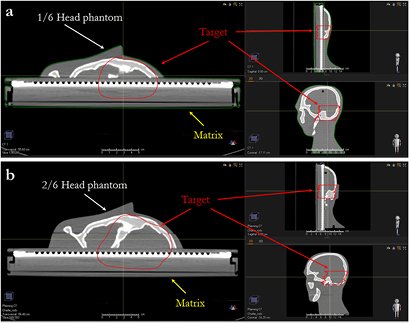

Standard image High-resolution imageFigure 2. Three projections of the target of the single slice (a) and two slices (b) of the anthropomorphic phantom lying on the MatriXX.

Figure 3. Three projections of the brain (a) and the nose target (b) of the lamb's head lying on the MatriXX.